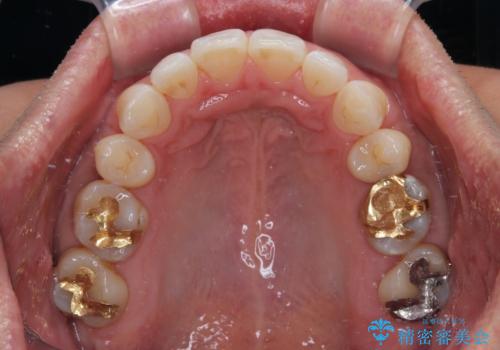

- 口元の突出感を気にして来院された患者様です。

強い咬合力と上顎前歯の傾斜により前歯が突出し、唇が閉じにくい状況であったため、上下左右の第一小臼歯4本を抜歯し、ワイヤー装置にて矯正治療を行うこととしました。

非常に咬合力が強いため、抜歯したスペースが閉じるのか不安でしたが、順調に歯が移動し、予定よりも早く治療を終えることができました。